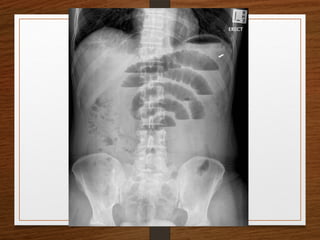

Sigmoid volvulus

The inverted U-shaped loop is usually massively distended

Commonly devoid of haustra, an important diagnostic point.

The ahaustral margin can often be identified overlapping respectively

 the lower border of the liver shadow (the liver overlap sign),

 the haustrated, dilated descending colon (the left flank overlap sign)

 the left side of the pelvis (the pelvic overlap sign).

The top of the sigmoid volvulus usually lies very high in the abdomen

(above the level of T10) with its apex on the left side.

Signs

 Grossly distended loop of sigmoid colon

 Coffee bean sign

 Air – fluid ratio > 2:1

 Lack of haustra

 Apex above 10th

thoracic vertebra

 Liver overlap sign

 Left flank overlap sign

 Pelvis overlap sign

 Bird of prey /twisted bird beak appearance

Sigmoid volvulus The invertedU-shaped loop is usually massively distended Commonly devoid of haustra, an important diagnostic point. The ahaustral margin can often be identified overlapping respectively  the lower border of the liver shadow (the liver overlap sign),  the haustrated, dilated descending colon (the left flank overlap sign)  the left side of the pelvis (the pelvic overlap sign). The top of the sigmoid volvulus usually lies very high in the abdomen (above the level of T10) with its apex on the left side.

• 31.

Signs  Grossly distendedloop of sigmoid colon  Coffee bean sign  Air – fluid ratio > 2:1  Lack of haustra  Apex above 10th thoracic vertebra  Liver overlap sign  Left flank overlap sign  Pelvis overlap sign  Bird of prey /twisted bird beak appearance